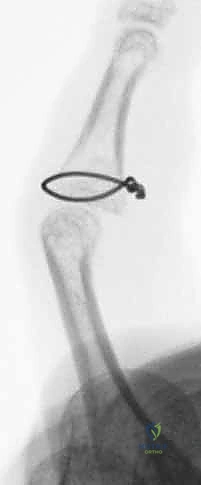

1. الرد المفتوح والتثبيت الداخلي (ORIF)

هذه هي الجراحة الكلاسيكية والمفضلة عندما يكون هناك قطعة عظمية واحدة كبيرة يمكن تثبيتها.

* الخطوات: يقوم الدكتور هطيف بعمل شق جراحي دقيق (عادة على شكل متعرج Bruner incision) للوصول إلى المفصل دون إتلاف الأوتار. يتم إرجاع العظم المكسور إلى مكانه التشريحي بدقة مجهرية.

* التثبيت: يتم تثبيت الكسر باستخدام مسامير تيتانيوم متناهية الصغر (Mini-screws بحجم 1.3 مم أو 1.5 مم) أو باستخدام أسلاك كيرشنر (K-wires). يضمن هذا التثبيت الصلب قدرة المريض على بدء تحريك إصبعه بعد أيام قليلة من الجراحة.